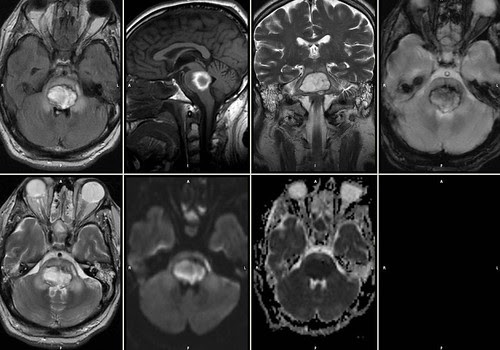

Aquí podeis ver una resonancia magnética de un hematoma protuberancial. El estudio de neuroimagen presentado consta de las secuencias: FLAIR axial, T1 sagital, T2 coronal, T2 eco de gradiente axial, T2 axial, difusión, mapa ADC.